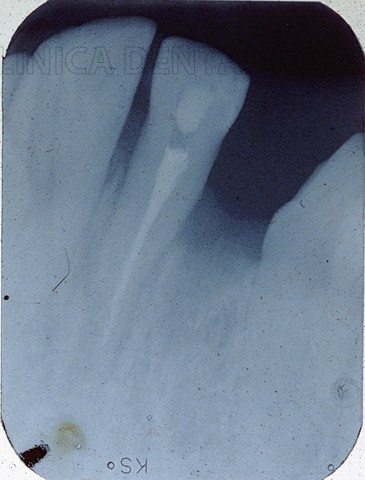

Exponemos un caso que por su  singularidad y dificultad de resolución merece su inclusión.

Se trata de un paciente que acude a nosotros con destrucción irreparable del incisivo central superior izquierdo y presenta un incisivo lateral del mismo lado en franca mordida cruzada.

Para evitar la pérdida del incisivo lateral (imposibilidad de realizar un puente fijo  en mordida cruzada),se procedió a la endodoncia “in situ” del citado incisivo siendo trasplantado instantes después en el  lecho del incisivo central extraído  y ferulizado posteriormente de manera elástica al incisivo central derecho de manera provisional.Se reforzó  mediante un espigo de oro- platino y procedimos al tallado del canino superior izquierdo.El resultado salta a la vista, un magnífico puente fijo de sólo tres piezas, con una única pieza perdida (el incisivo central izquierdo),se  minimiza la pérdida ósea secundaria a toda extracción dental (eliminamos una pieza , no dos).

Se aportan radiografías en las que no se visualiza anquilosis radicular ni reabsorción secundaria.

El caso ilustra sobradamente las estrategias seguidas antes del auge implantológico y hace gala de una elevada experiencia y conocimientos profesionales.